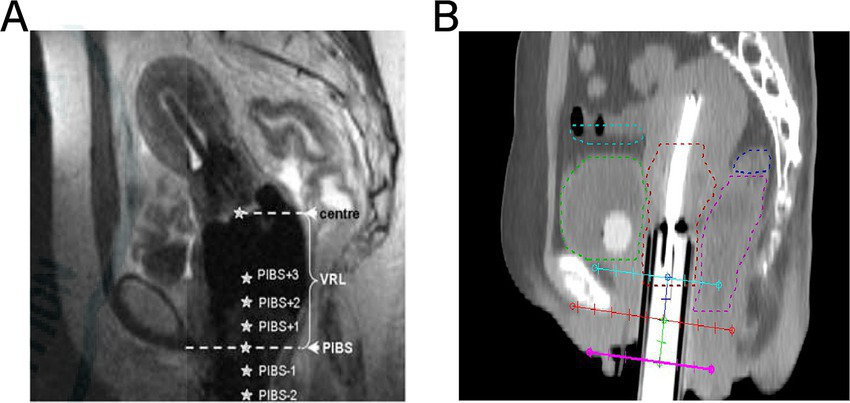

2.2.4 PIBS point dose

PIBS system is described in the literature (16). It is the point where the PIBS line intersects perpendicularly with the uterine applicator, representing the middle and lower thirds of the vaginal junction, as well as the level of the clitoris and anal sphincter, as shown in Figure 1A. The PIBS-2 point refers to the location of the 2 cm lateral to the pedicle along the uterine canal, marking the vaginal opening. The PIBS+2 point refers to the location of the 2 cm cephalad along the uterine canal, representing the midpoint of the vagina. Since the mucosal surface dose is prone to overlap with the target area, potentially leading to overdose, the submucosal 5 mm depth was used as the dosimetry point in this study, as shown in Figure 1B.

Figure 1

www.frontiersin.org

Figure 1. PIBS point dose: (A) shows the location of PIBS in cervical cancer; (B) shows the location of the selected PIBS point dose in this study.